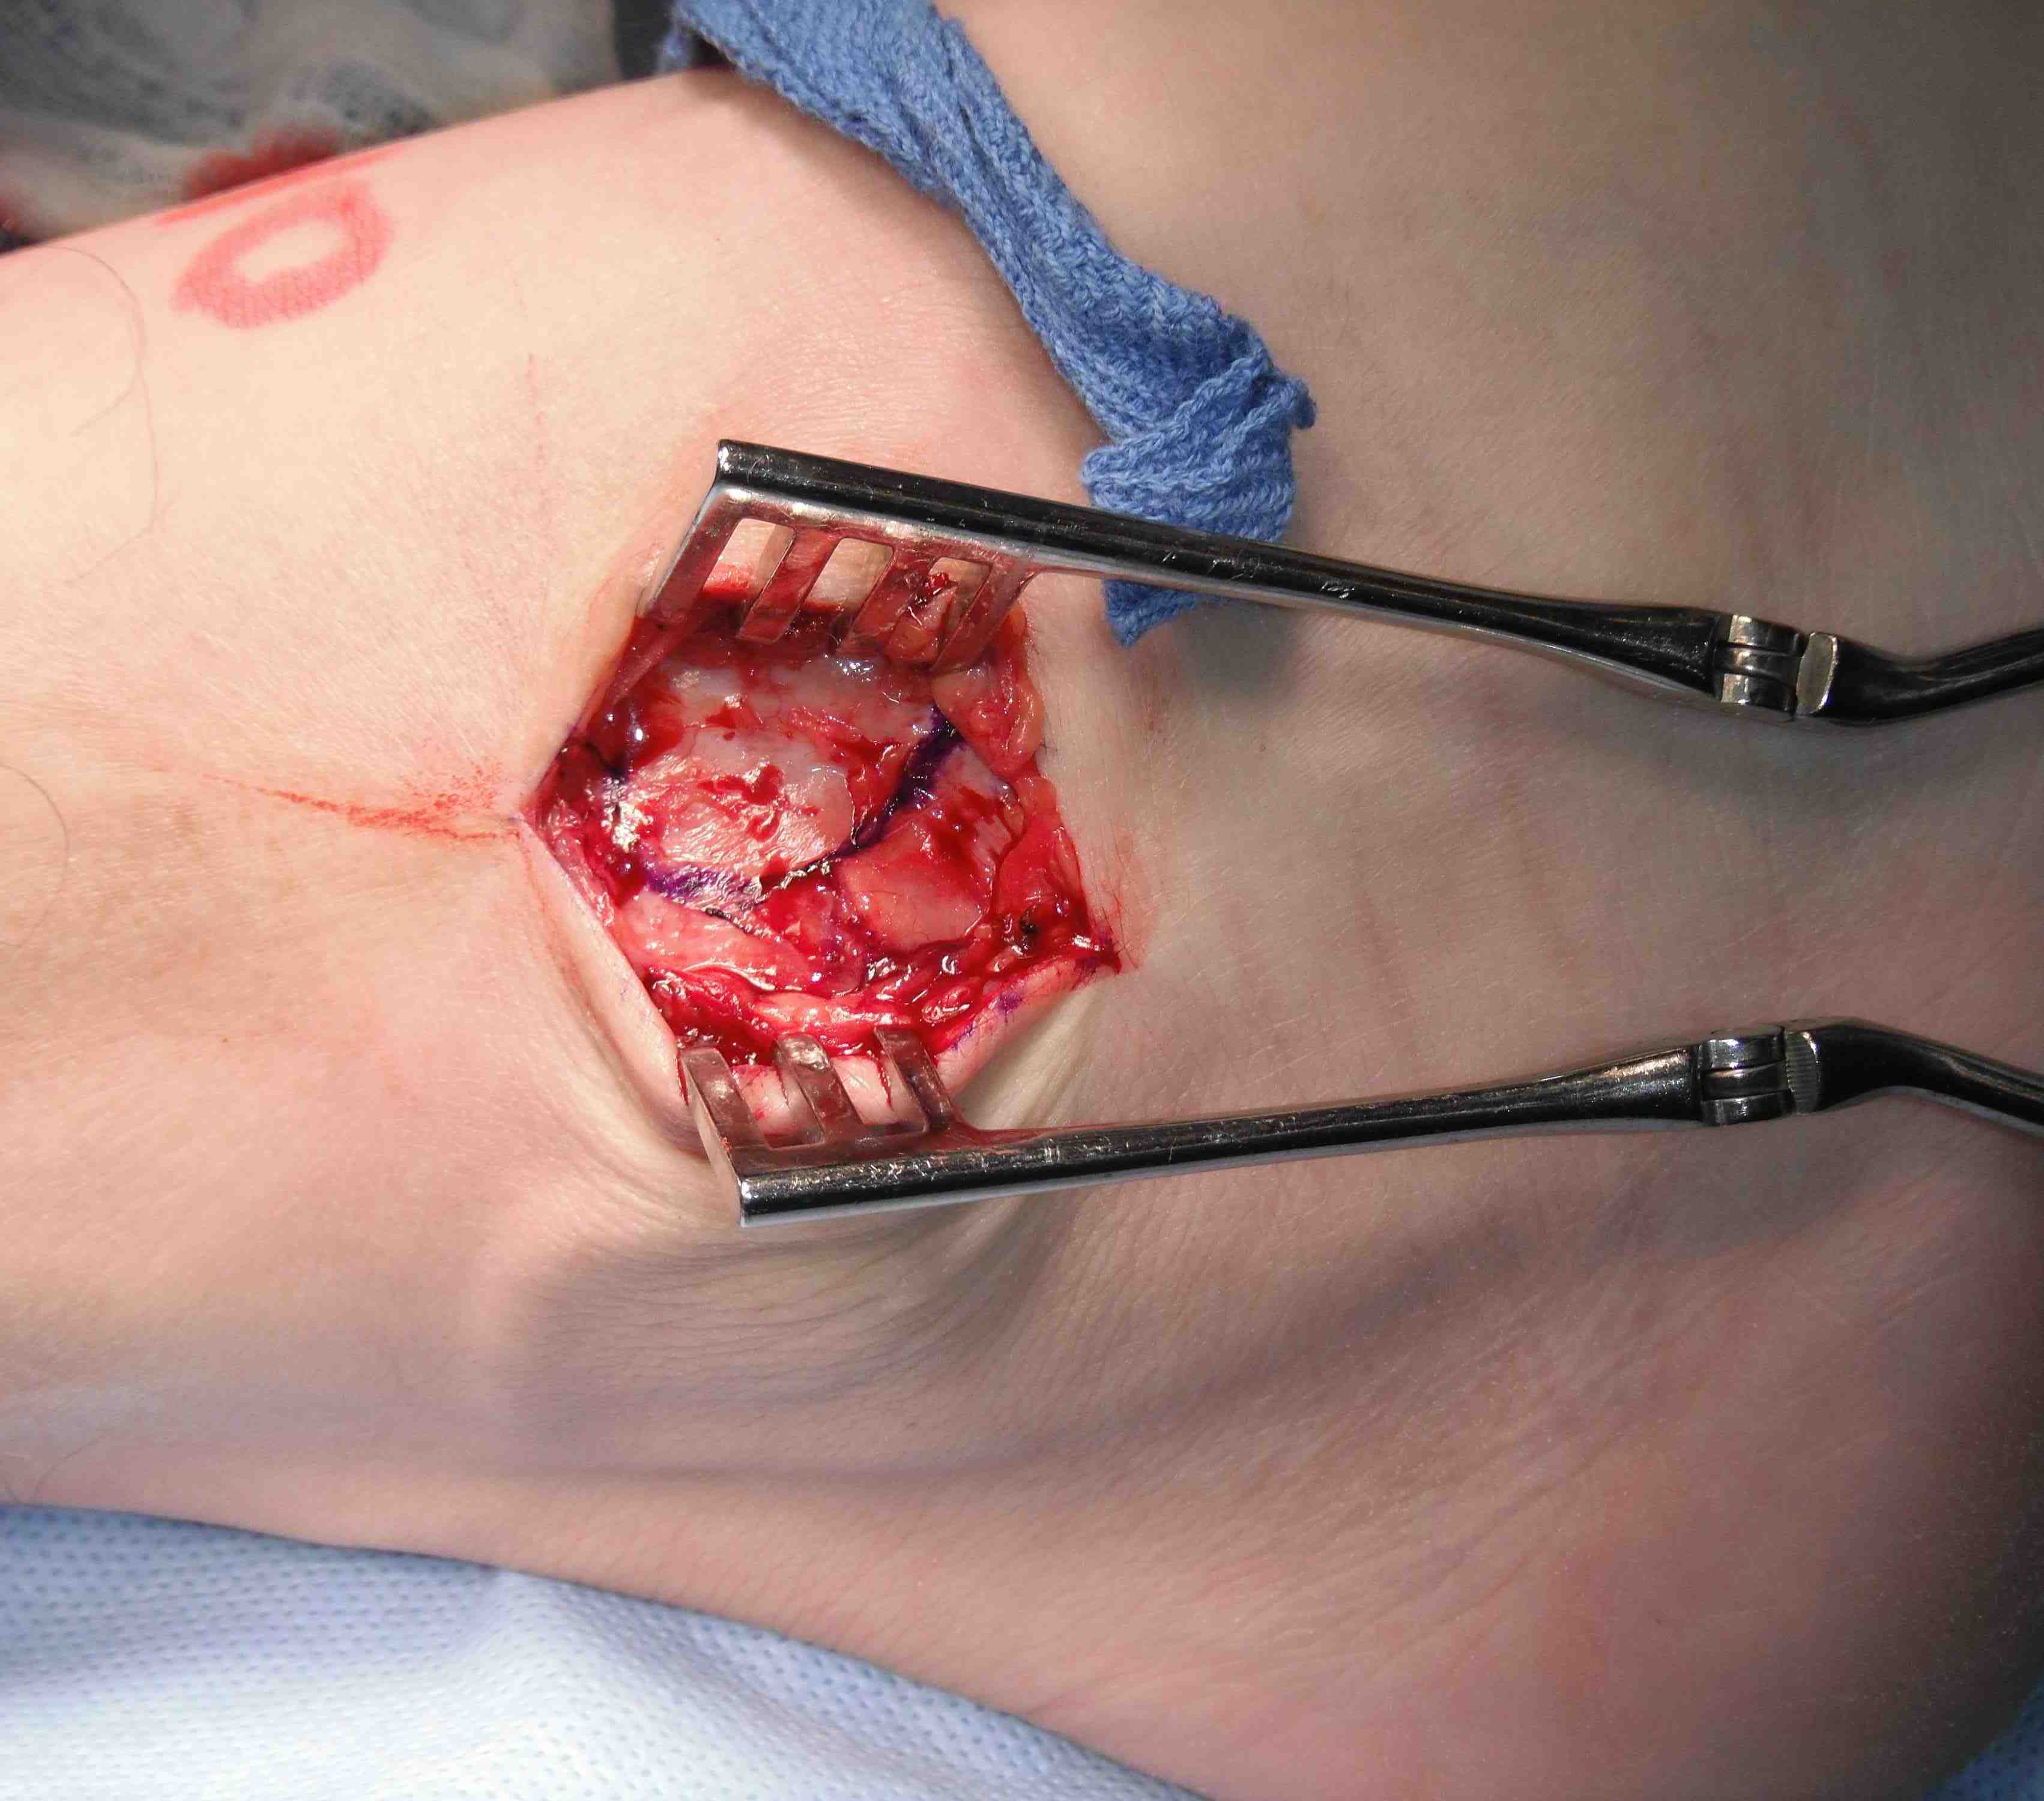

Open technique

Longitudinal incision anterior to lateral malleolus

- protect branches of superficial peroneal nerve

- expose tissue of ATFL / CFL

- anterior incision between ATFL and CFL to talus

- begins at tip of fibula to talus

- take off fibula as broad / thick flap

- superior flap is ATFL / inferior flap is CFL

- need to protect peroneals with inferior portion of dissection

- inspect talus for chondral damage

Place foot in eversion and AJ neutral

- 2 x 3.5 mm anchors in fibula

- ensure not in joint and not prominent

- 4 sutures through ATFL

- 2 through CFL

- 2 sutures either side of interval of ATFL and CFL

Gould modification

- advance the inferior retinaculum and suture to the fibular to reinforce the repair